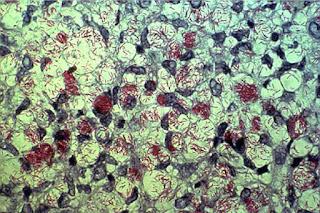

Now, let’s take a broader look at this disease. Leprosy, also referred to as Hansen’s disease, is a bacterial infection primarily affecting the skin and peripheral nervous system, caused by Mycobacterium leprae (or the newer M. lepromatosis).

Although leprosy is not highly contagious, transmission can occur through contact with an infected person’s lesions or through respiratory droplets during frequent contact with untreated cases.

Common symptoms of leprosy are discolored spots and rashes, foot ulcers, facial swelling, numbness, and potential paralysis. The disease can cause nerve damage, leading to a decreased sense of pain and unnoticed lesions in other body parts.